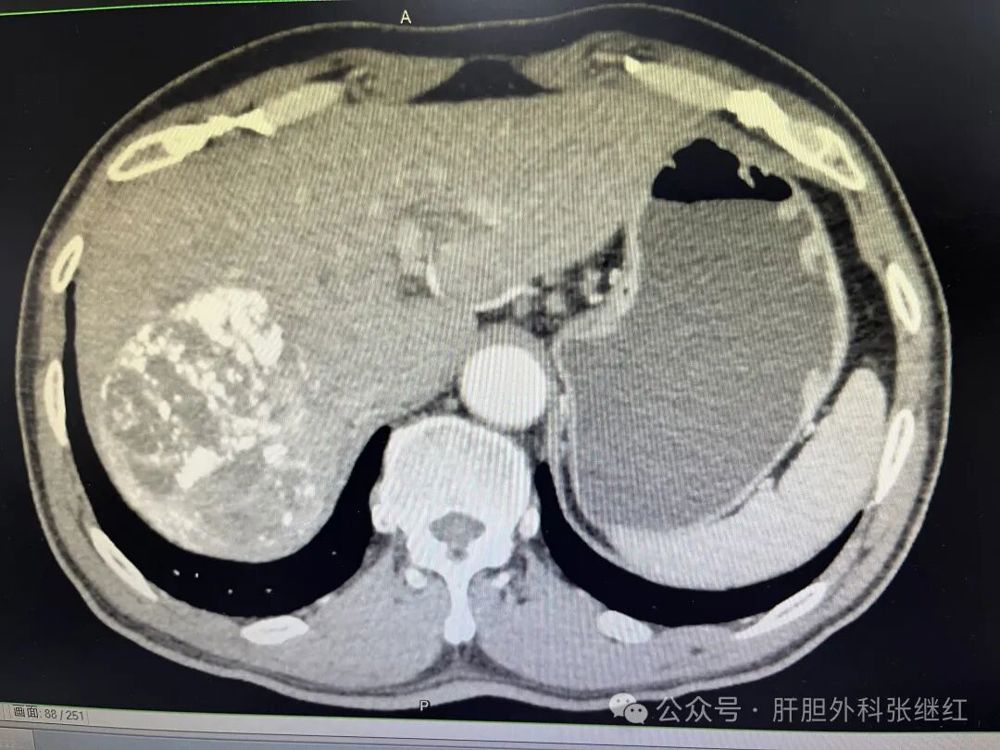

术后一周CT